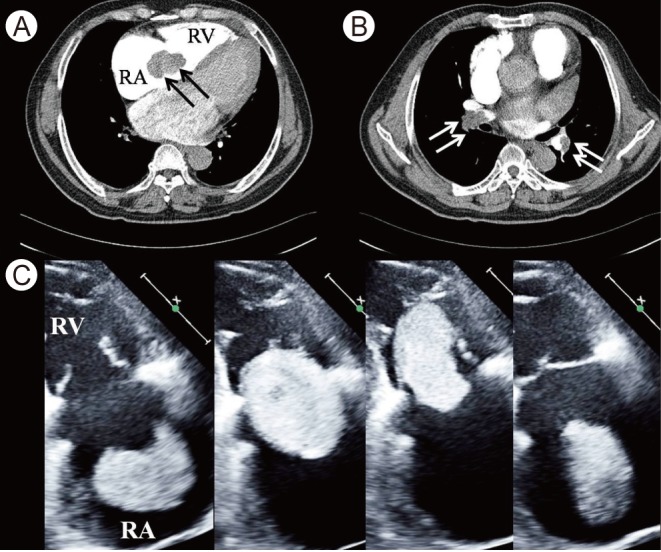

Figure 1

(A, B) Computerized tomographic images showing a mass floating in the right heart (A, black arrows) and embolism in both pulmonary arteries (B, white arrows). (C) A series of echocardiographic images of the right heart. A huge deformable echogenic mass in the enlarged right atrium (RA) is floating and plugging the right ventricle (RV) during diastole (the first three images) and ejected out during systole (the last).

A 62-year-old man suffered from exertional dyspnea and repetitive momentary dizziness that began occurring just after forceful chest beating to end an episode of acute shortness of breath 3 days prior. His blood pressure was 102/66 mmHg. His D-dimer level (435 µg/L) and N-terminal pro-brain natriuretic peptide level (2,863 pg/mL) were elevated. Electrocardiography exhibited atrial fibrillation with a regular junctional rhythm and a rate of 56 bpm. An intracardiac mass and acute thromboembolism in both pulmonary arteries (APTE) were diagnosed by computed tomography (Fig. 1A and 1B). Echocardiography revealed a very large 60 × 50 mm deformable mass f loating freely in the markedly enlarged right atrium (RA), plugging the right ventricle through the tricuspid valve and periodically occupying the entire cavity (Fig. 1C). Emergent surgery was performed to remove the mass and the APTE. The RA mass was a Chinese moon cake-like thrombus (65 × 55 × 20 mm) (Fig. 2). Two remnant stalks were found on the RA wall. Pathology confirmed that the mass was an organized thrombus and that the stalks were degenerative muscular tissue.